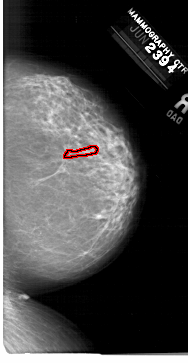

A_1330_1.LEFT_MLO

LEFT_MLO LINES 6601 PIXELS_PER_LINE 4306 BITS_PER_PIXEL 12 RESOLUTION 43.5 NON_OVERLAY

FILE: A_1330_1.RIGHT_MLO.OVERLAY

TOTAL_ABNORMALITIES 1

ABNORMALITY 1

LESION_TYPE CALCIFICATION TYPE PLEOMORPHIC DISTRIBUTION LINEAR

ASSESSMENT 4

SUBTLETY 2

PATHOLOGY BENIGN

TOTAL_OUTLINES 1

BOUNDARY